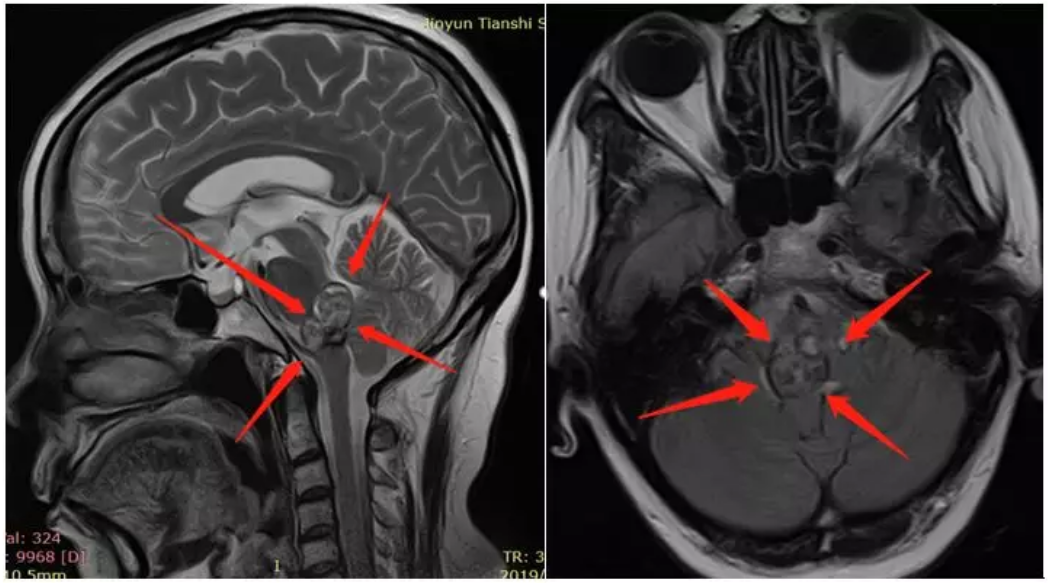

术前诊断:脑干脑桥海绵状血管瘤,出血活动期,压迫第四脑室

术后48小时内MR复查显示肿瘤全切